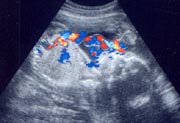

胎児の大きさ(妊娠23週末)☆身長/約30cm ☆体重/約700g

体の発育のスピードはめざましくなります。身長、体重が大きくなって、赤ちゃんの体全部が超音波のモニター画面に映るのはむずかしくなってきて、画面には頭と胸のところ、おなか、足や手など、部分的にしか映らないようになってきます。

超音波で赤ちゃんの体重を推定する場合には、頭の横幅(児頭大横径)、おなかの横断面の面積(左右径と前後径)、大腿骨の長さ(大腿骨長)の3つを測り、この数値をもとに算出します。